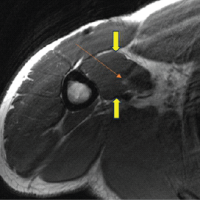

Our case adds to the limited literature on BASD secondary to epileptic seizures by documenting a successful closed reduction and early physiotherapy without surgical intervention, achieving near full functional recovery at 3 months [1,2,9]. Unlike some reports that recommend magnetic resonance imaging (MRI) to assess soft tissue injury or associated rotator cuff tears, we did not perform MRI as the patient had no clinical signs suggestive of rotator cuff pathology or neurovascular deficits, and immediate radiographs confirmed stable concentric reduction [1,2,7,9]. Since there was no recurrence of an instability episode, MRI was deferred. This approach aligns with conservative management principles for uncomplicated BASD cases where radiographs suffice for decision-making, and MRI is reserved for suspected complications or recurrent cases [1,2,5,8].